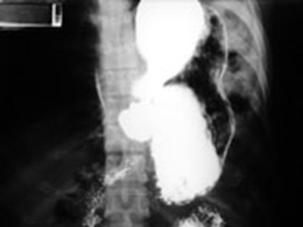

Perforatie

esofagiana Leziune de

hemidiafragm drept

Pneumomediastin

Leziune de hemidiafragm drept Leziune de hemidiafragm stang

Ruptura de hemidiafragm stang cu hernierea Ruptura de hemidiafragm stang cu hernierea

stomacului si splinei stomacului si splinei.Imagine CT

Ruptura de

hemidiafragm stang cu hernierea Ruptura de diafragm

stomacului si splinei Radiografie cu substanta de contrast

Ruptura de diafragm Ruptura de diafragm. Gastrotorax

Ruptura de diafragm. Gastrotorax Imagine CT